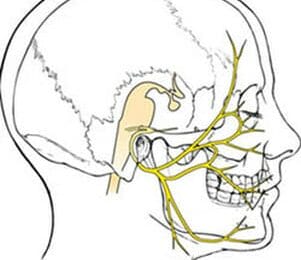

Hersenzenuwen

Onze hersenen zijn een fascinerend orgaan, hetgeen niet...